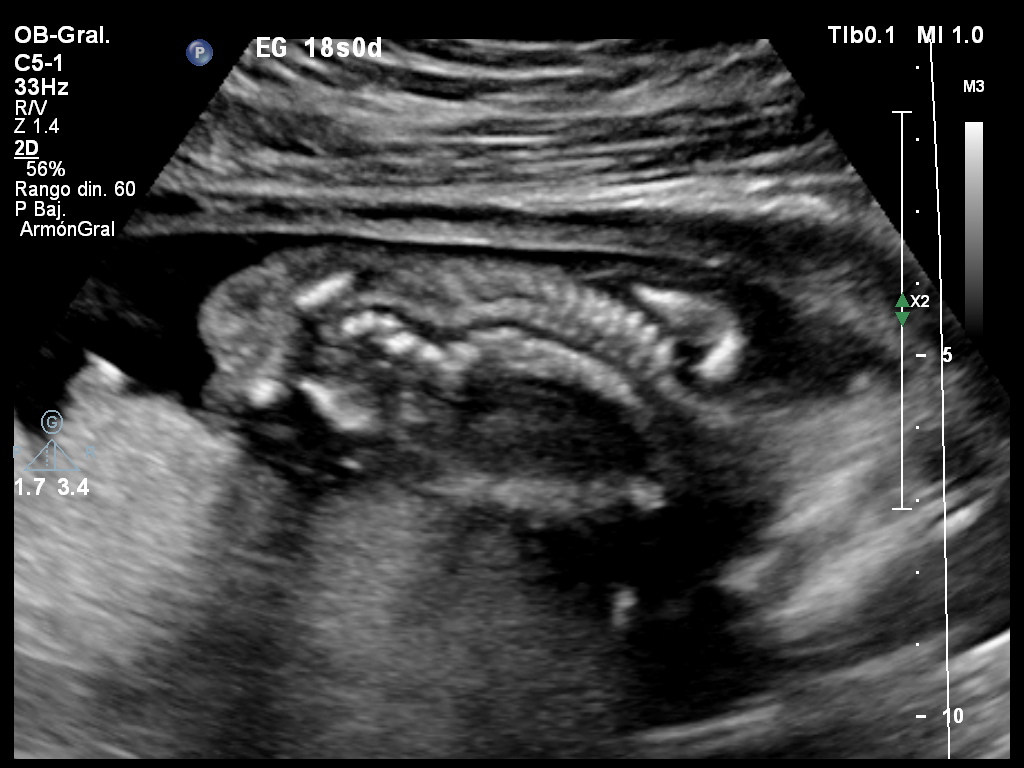

Se presenta a la consulta una paciente primigesta de 24 años, cursando un embarazo de 18 semanas de gestación. No adjunta estudios realizados previamente. Refiere no haber realizado el screening ecográfico de aneuploidías. En la ecografía se constatan los siguientes hallazgos: Figura 1. A: corte axial de un asa de cordón libre (flecha amarilla); B: corte axial de pelvis fetal a nivel de la entrada del cordón umbilical. Figura 2. Corte longitudinal de la pierna fetal. Se observa uno de los huesos largos de la pierna y la planta del pie homolateral. Figura 3. Corte coronal de la columna fetal. Se observa la desviación de la misma hacia la derecha. Figura 4. Corte axial de columna fetal. Se observa la ausencia de apófisis vertebral posterior unilateral. Elija la opción correcta: • Solicita una ecografía obstétrica detallada y ecocardiograma fetal por la probabilidad de que se trate de un síndrome genético de expresión variable. • Tranquiliza a los padres confirmando el origen benigno de los hallazgos con probable solución ortopédica luego del nacimiento. • Deriva con carácter de urgencia a realizar asesoramiento genético por tratrarse de una probable displasia esquelética letal.

Respuesta correcta: A) Solicita una ecografía obstétrica detallada y ecocardiograma fetal por la probabilidad que se trate de un síndrome genético de expresión variable.